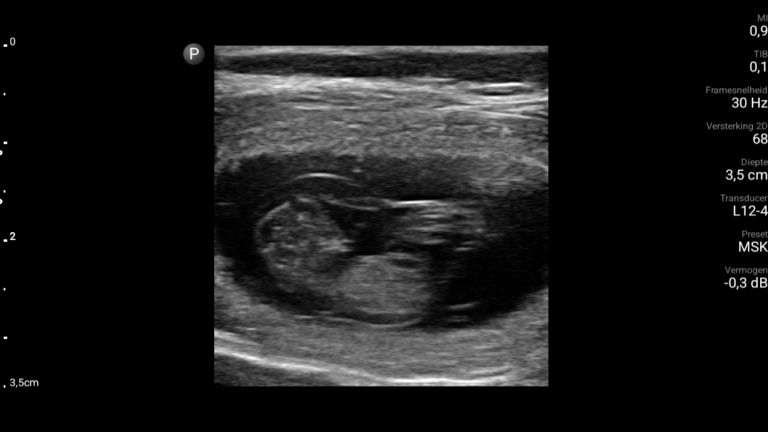

Op 3 mei 2024 was het dan eindelijk zover, de dag van de echo. Bij de echo zagen we meteen het eerste pupje en wisten we gelijk, ZE IS DRACHTIG! Wat was het bijzonder om de kleine pupjes te zien en de hartslagjes te horen.

Echo dag 32